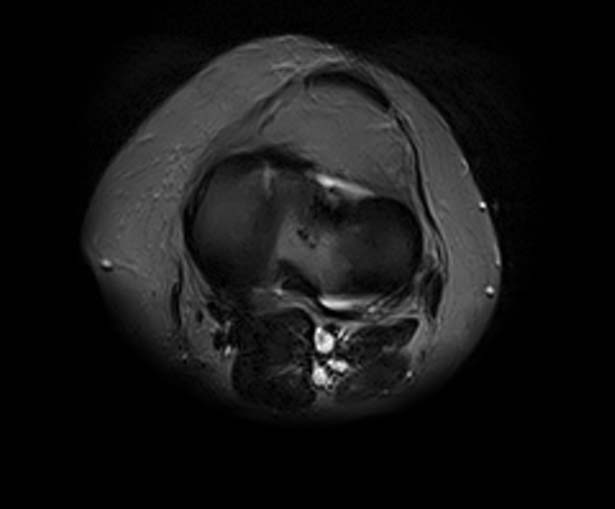

[Ortho] Показания для артроскопии

1. травма 5 лет назад - "ударилась коленом", с тех пор боли в суставе

3. стандартные рентгенограммы с небольшими изменениями - сужение

медиальной суставной щели

5. сустав клинически стабилен